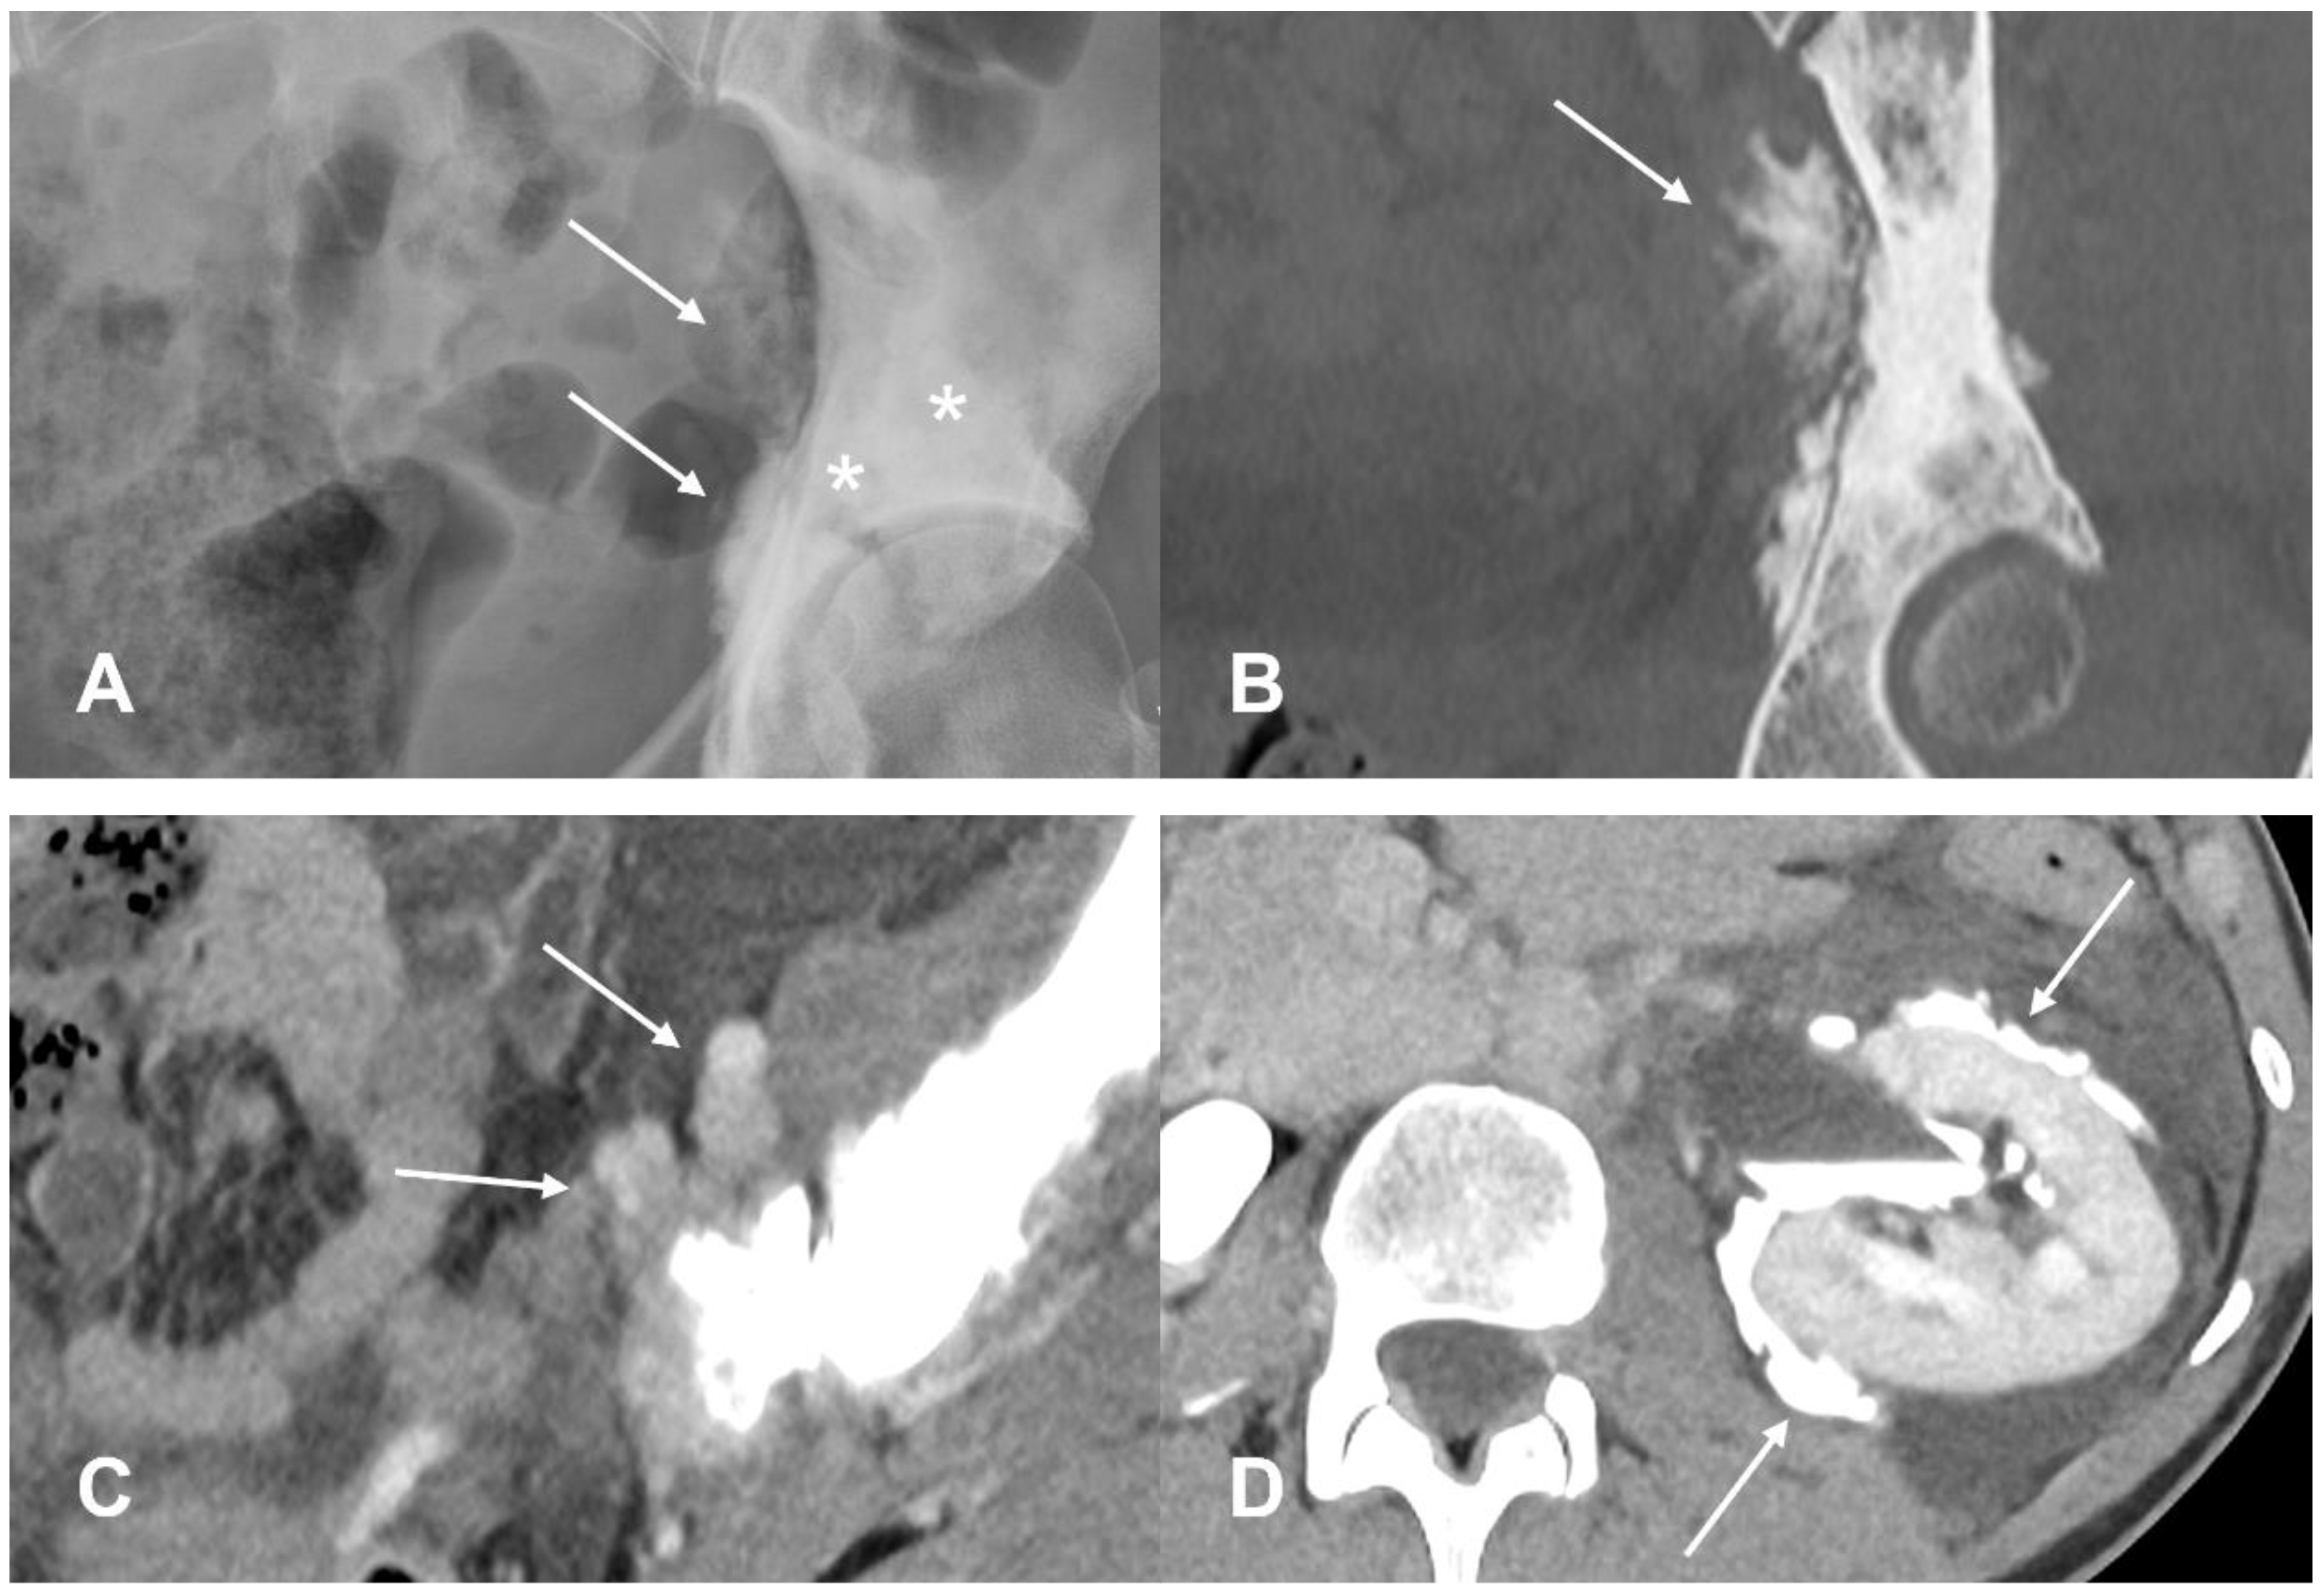

3.2.1. Parosteal Osteosarcoma

- Hang, J.-F.; Chen, P.C.-H. Parosteal Osteosarcoma. Arch. Pathol. Lab. Med. 2014, 138, 694–699. [Google Scholar] [CrossRef]

- Harper, K.; Sathiadoss, P.; Saifuddin, A.; Sheikh, A. A Review of Imaging of Surface Sarcomas of Bone. Skeletal Radiol. 2021, 50, 9–28. [Google Scholar] [CrossRef] [PubMed]

- Jelinek, J.S.; Murphey, M.D.; Kransdorf, M.J.; Shmookler, B.M.; Malawer, M.M.; Hur, R.C. Parosteal Osteosarcoma: Value of MR Imaging and CT in the Prediction of Histologic Grade. Radiology 1996, 201, 837–842. [Google Scholar] [CrossRef] [PubMed]

- Okada, K.; Frassica, F.J.; Sim, F.H.; Beabout, J.W.; Bond, J.R.; Unni, K.K. Parosteal Osteosarcoma. A Clinicopathological Study. J. Bone Joint Surg. 1994, 76, 366–378. [Google Scholar] [CrossRef] [PubMed]

- Campanacci, M.; Picci, P.; Gherlinzoni, F.; Guerra, A.; Bertoni, F. Neff Parosteal Osteosarcoma. J. Bone Joint Surg. Br. 1984, 66-B, 313–321. [Google Scholar] [CrossRef] [PubMed]